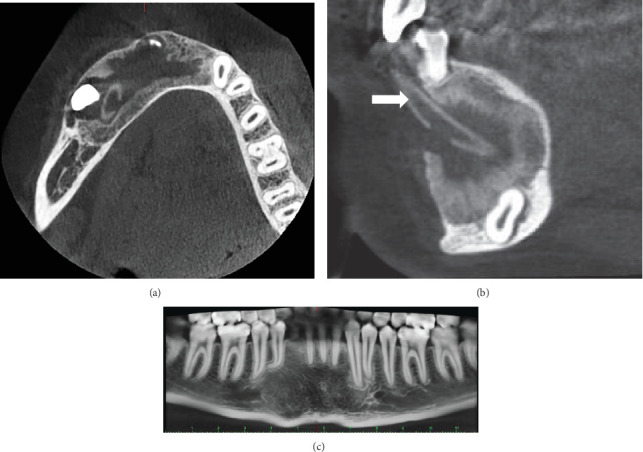

A calcifying odontogenic cyst (COC) is a cystic lesion originating from odontogenic epithelium, exhibiting ameloblastomatous features and containing focal accumulations of ghost cells. The standard treatment for COC typically involves enucleation followed by surgical curettage. However, if the cyst is large or closely associated with anatomical structures, decompression may be considered as a preliminary step before enucleation. A 12-year-old male patient presented with swelling in the anterior mandibular region. Radiological assessment revealed an extensive radiolucent area crossing the mandibular midline, accompanied by radiopaque areas within the lesion. The diagnosis of COC associated with compound odontoma was confirmed. The treatment plan involved decompression, followed by enucleation. After over 9 years of follow-up, the patient showed satisfactory and effective outcomes, with no signs of recurrence. This therapeutic approach minimizes the morbidity and cost associated with extensive and invasive reconstructive surgeries.